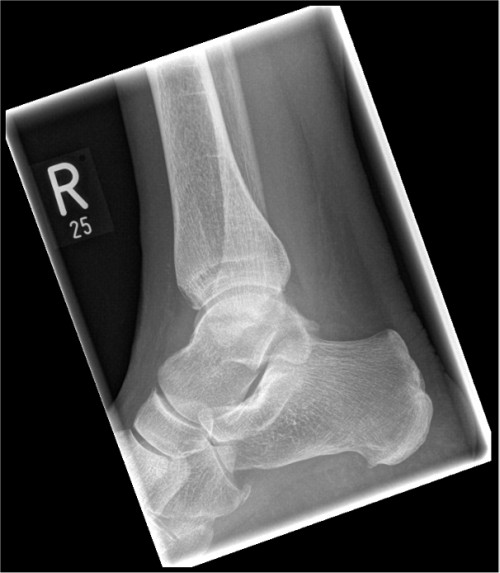

ICD: S82.5

ICD: S92.0

Eine 66-jährige Patientin stellt sich in der Notfallambulanz vor und berichtet von einer Leiter gestürzt zu sein. Sie habe für ihren Enkel Lego-Spielzeug vom Dachboden holen wollen und sei dabei von der Leiter gerutscht. Sie sei auf ihren beiden Fersen gelandet und anschließend auf den Rücken gefallen. Der linke Fuß sei seitdem nicht belastbar, der rechte Fuß schon. Am rechten Fuß sei jedoch eine Schwellung im Bereich der Sprunggelenke sichtbar geworden.